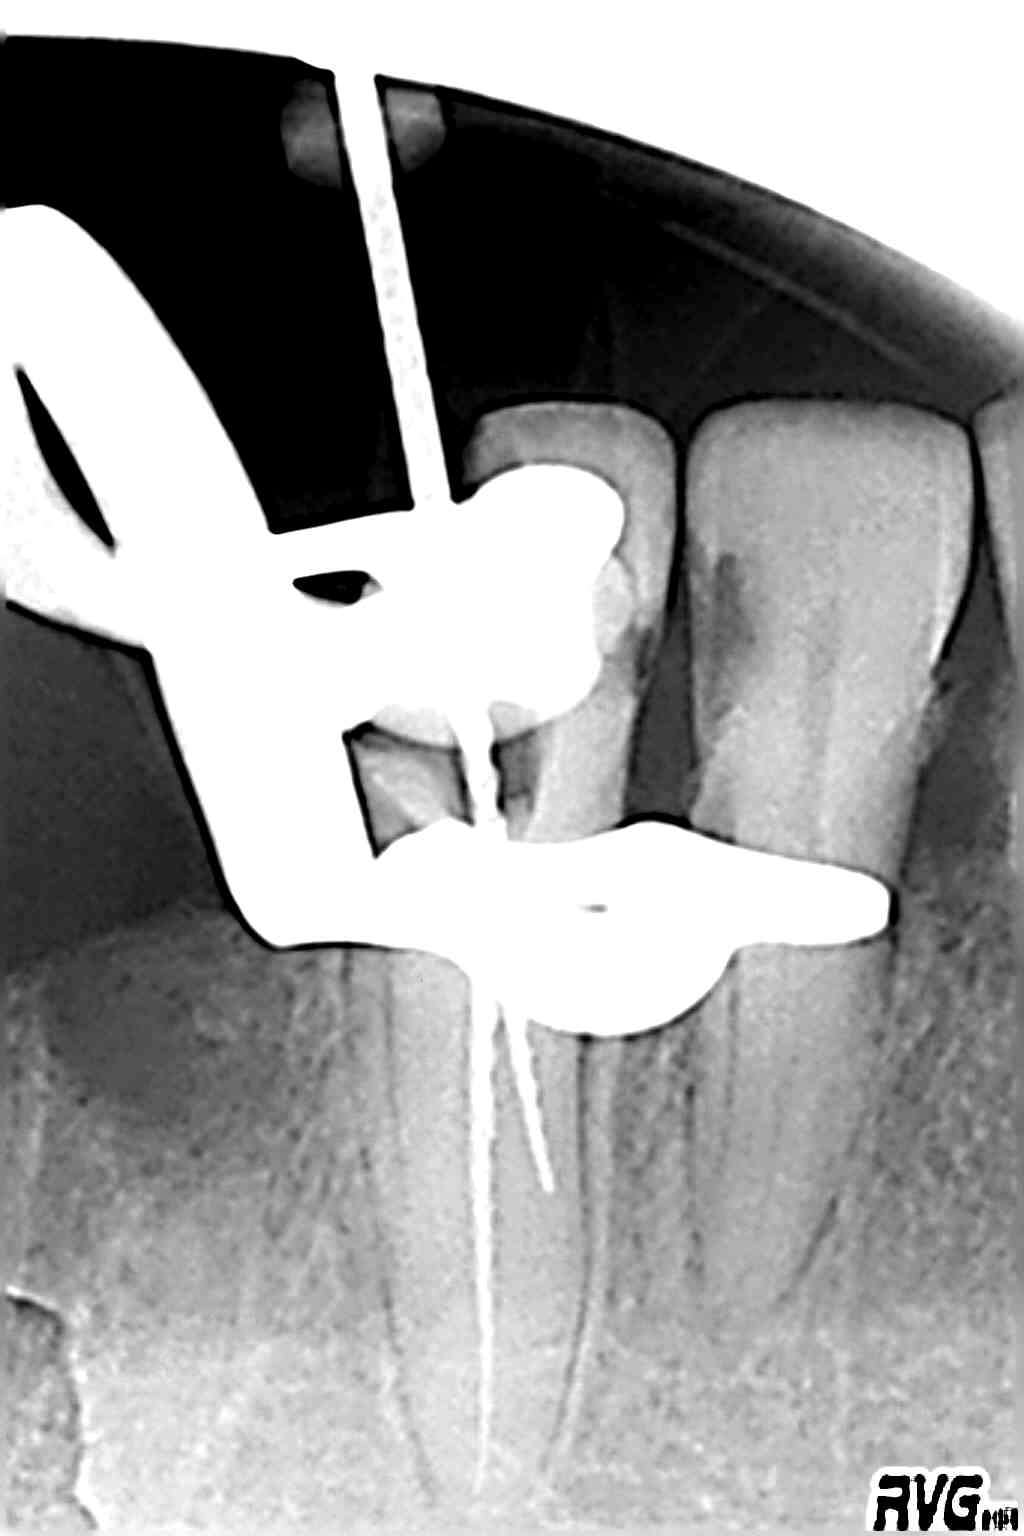

Pff la même ... en pire, je pète un instru, parce que je ne pensais pas couronner (pas un rond, d'autres trucs à faire ... ), du coup je n'ouvre pas assez la cavité d'accès ... et crac ... pété à l'apex, impossible à virer.

Bon je tente un by pass ... et voilà le résultat, je pense m'arrêter avant la perf mais c'est pas chouette :(

le vissage est plus loin du genre apex-5mm

sur la RVG tu vois la lime 15 engagée le long de l'instrument sur 2/3 de sa longueur

Une F1 travaille sur son 1/4 inférieur, le vissage est probablement là. Le gros soucis avec le NiTi c'est que la lime se déforme avant de casser, c'est un vissage "sous contrainte élastique" (je ne sais le formuler autrement), et non un simple vissage/blocage. Belle galère.